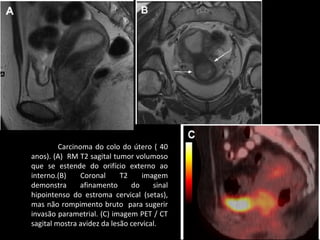

Carcinoma do colo do útero ( 40

anos). (A) RM T2 sagital tumor volumoso

que se estende do orifício externo ao

interno.(B)

Coronal

T2

imagem

demonstra

afinamento

do

sinal

hipointenso do estroma cervical (setas),

mas não rompimento bruto para sugerir

invasão parametrial. (C) imagem PET / CT

sagital mostra avidez da lesão cervical.